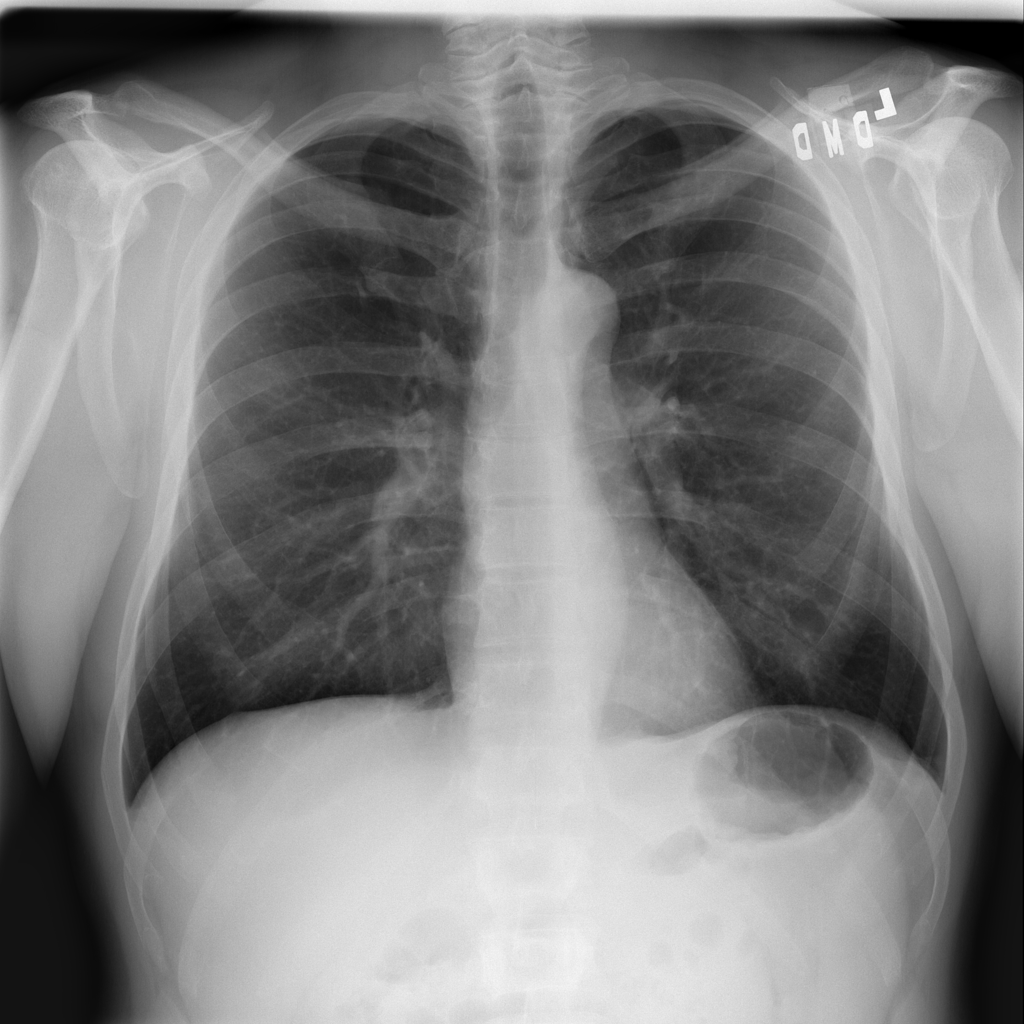

PAT-C255 · IMG-000Emphysema

PAT-C255 · IMG-000

PA